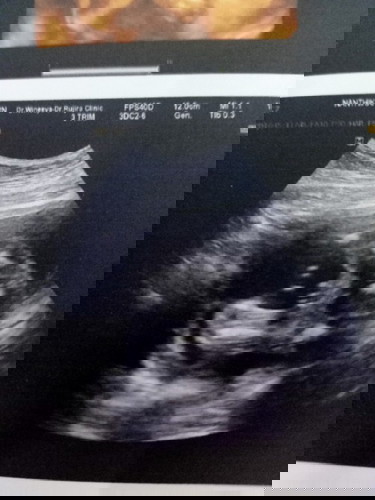

แบ่งปันภาพอัลตราซาวด์เพศตัวเล็กกันค่ะ😍

แบบนี้ ผช แน่ๆใช่ไหมคะ😆 ขอดูรูปอัลตราซาวด์เพศน้องของแม่ๆหน่อยค่ะ มีบ้านไหน เห็นส่ยสะดือพร้อมเพศแบบนี้ไหมคะ🥰

น่าจะชายนะค่ะ